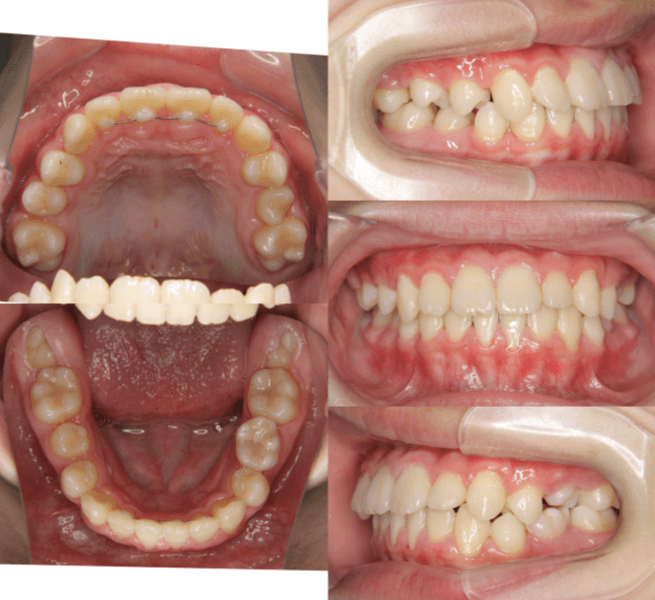

| 年齢・性別 | 8歳3ヶ月の男児 |

|---|---|

| 主訴 | 上顎前歯の位置異常に不安を抱え、歯並びと将来的な咬合状態を整える目的で来院された患者様です。 特に左側の前歯(中切歯および側切歯)の萌出が確認できないことがきっかけとなりました。 |

| 治療期間・回数 | 約5年10ヶ月 |

| 費用 | 460,000円(税別) |